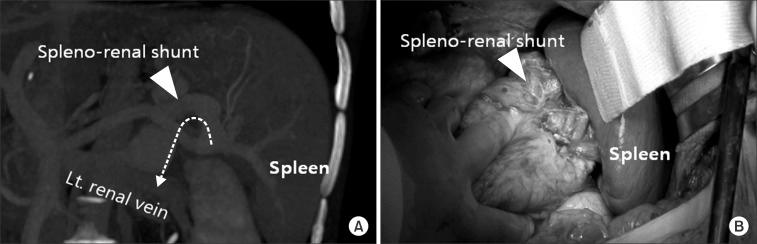

Benign portal vein thrombosis (PVT) is a challenging complication of an otherwise successful liver transplantation. PVT is caused by various conditions and results in pathologic hemodynamics of hepatofugal diversion of porto-mesenteric blood flow. Thus, adequate restoration of portal blood flow to the liver graft is a major concern when trying to achieve successful liver transplantation in patients with PVT. This letter describes the surgical view point of PVT in liver transplantation.

良性门静脉血栓形成(PVT)是成功进行肝移植后一种具有挑战性的并发症。PVT由多种情况引起,会导致门静脉 - 肠系膜血流出现离肝性分流的病理性血流动力学改变。因此,在试图对患有PVT的患者成功进行肝移植时,充分恢复移植肝的门静脉血流是一个主要关注点。本文从外科角度描述了肝移植中PVT的情况。